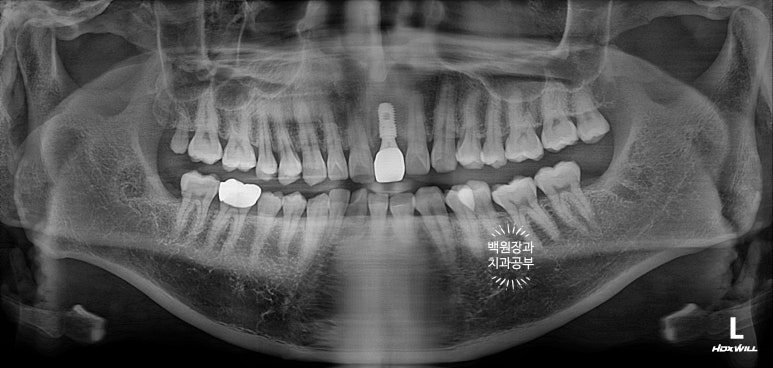

엑스레이를 보시면, 내원 당시 기둥까지 빠졌던 치아를 그 자리에 끼워놓으셨기 때문에 마치 치아가 멀쩡한 것 처럼 보입니다만, 이미 사용하기 어려운 지경의 상태였습니다.

뽄뜨는 날 임플란트와 주변 뼈와의 관계를 평가하기 위해

작은 치근단 촬영도 함께 시행하는데요,

임플란트 주변의 뼈와 이식된 뼈이식재들이 잘 유지됨을 간접적으로 확인할 수 있었습니다.

사실 엑스레이로 찍어놓으면 엄청 임플란트 그 자체입니다.!!!

적절히 가운데에 심겨진 임플란트 덕분에 자연스러운 보철물을 만들 수 있었습니다.